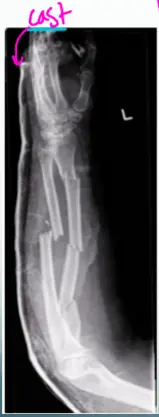

- x-ray AP and lateral view of forearm, show a displaced fracture in both radius and ulnar shaft with elbow dislocation

- cast, slab, splint, traction pin, implants

Cast

- X-ray AP view of Lt femur, fracture of distal femur with slab, Thomas splint

- X-ray AP view of Rt distal femur, presence of traction pin

- X-ray AP view of Lt femur, fracture in distal femur with plate and screws